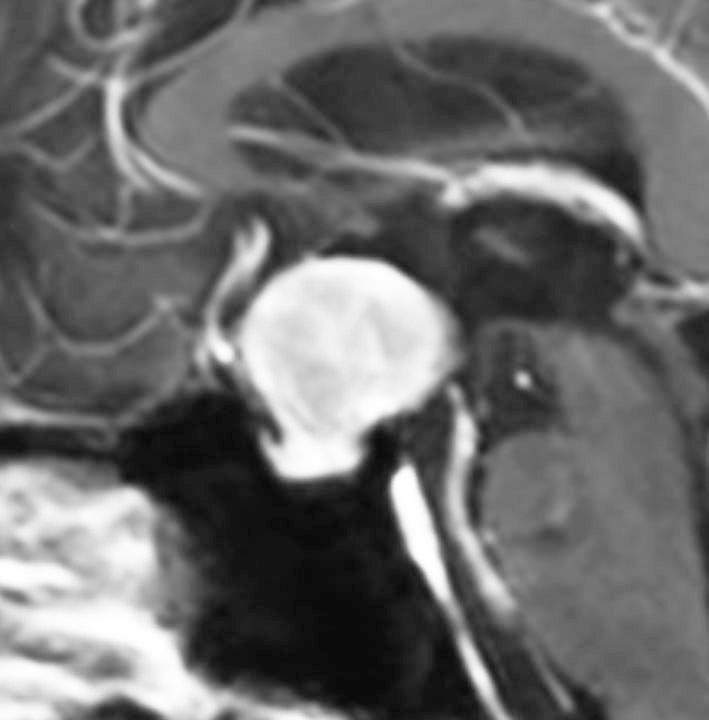

40代の女性に,軽度の両耳側半盲で発生したものです。視交叉と視床下部の下面に腫瘍があり,下垂体柄の位置が全くわからず,下垂体の前葉と後葉は侵されていません。ですから,下垂体柄から発生した腫瘍であり,pituicytomaが強く疑われます。T2ではほぼ等信号,小さなのう胞があり,ガドリニウムで強く増強されます。手術では正常下垂体柄の一部が右側にうすく残っており,幸運にも亜全摘出できて下垂体機能は温存できました。残存腫瘍は増大傾向を示していません。でも,このようなタイプを積極的に摘出すると,汎下垂体機能低下症を招くことが多いので,手術するかどうかの判断はとても難しいです。

下垂体後葉腫瘍の典型的な画像です。下垂体柄(黄色の矢印)が伸びて前方へ偏移しています。またその直下に下垂体前葉(強い白の部分)がみえます。

ジャーミノーマでは下垂体柄も同時に太くなるのでジャーミノーマは否定的な所見です。

- 画像上は境界が明瞭な腫瘍です

- 腫瘍内部にvascular voidsが多く見えて激しく出血する腫瘍です